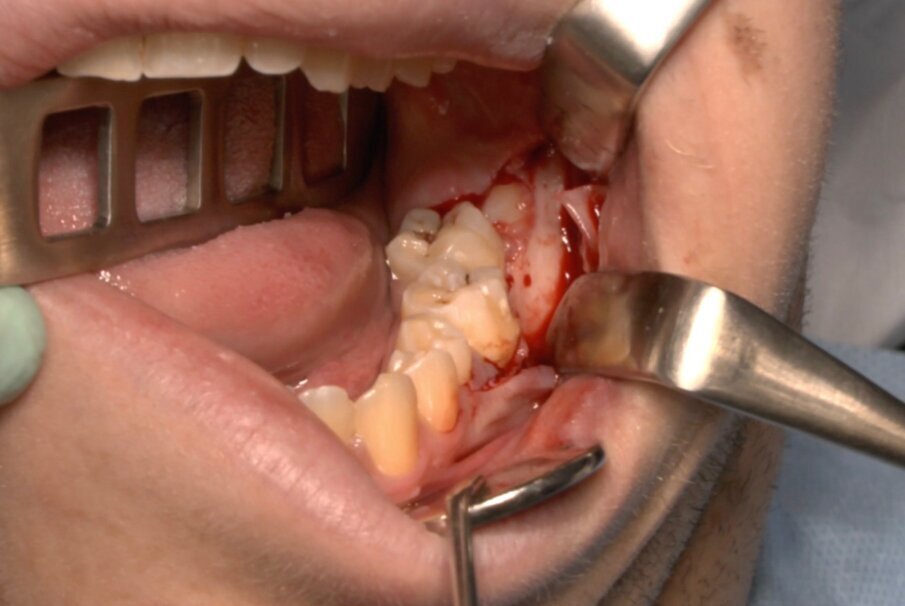

Protocollo standard

Ai pazienti viene prescritta una profilassi antibiotca con 2 gr di amoxicillina 1 h prima dell’intervento, si esegue quindi un anestesia di tipo tronculare con lidocaina senza vasocostrittore, poi infiltrazione di tipo plessica con adrenalina in corrispondenza del nervo buccinatore. Si scolpisce quindi un lembo a tutto spessore di tipo triangolare con incisione orizzontale alla base delle papille tra sesto e settimo ed incisione di scarico distale con andamento vestibolare (Figg. 1-4). Si procede con l’osteotomia che può essere eseguita con strumenti rotanti montati su manipolo retto oppure con terminale piezoelettrico con gli inserti dedicati. Qualora sia necessario si effettua l’odontotomia e la separazione radicolare con frese al carburo di tungsteno montate su turbina, quindi si esegue la lussazione e l’avulsione dell’elemento dentario. Si procede alla revisione della cavità alveolare con abbondante lavaggio con soluzione fisiologica, riempimento con collagene e sutura a punti staccati in seta 4/0. Il paziente viene dimesso con terapia analgesica ed antibiotica di supporto (Figg. 5-15).

Fig. 4_Scheletrizzazione con visione della corone del 3.8.